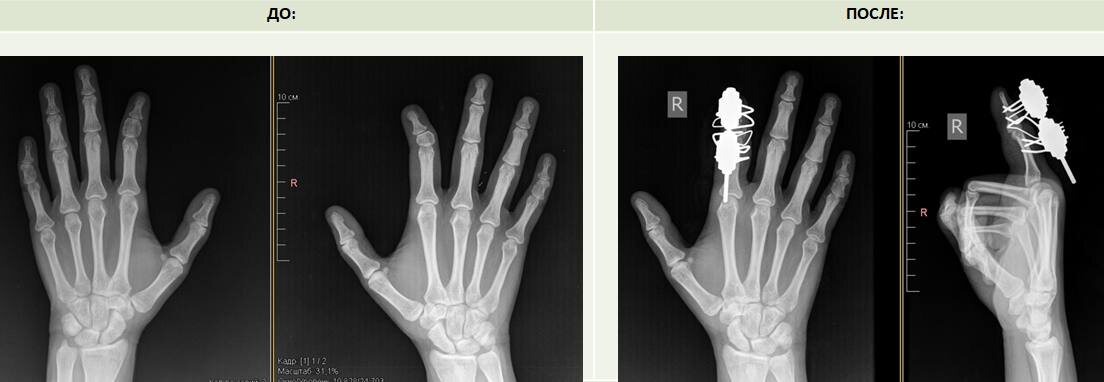

👩‍⚕️ В НМИЦ травматологии и ортопедии имени Г.А. Илизарова обратились сестры-близнецы с одинаковой врожденной патологией кисти — клинобрахидактилией. Это редкая аномалия, при которой укорочены средние фаланги пальцев и возникает угловая деформация.

👉 У пациенток были затронуты второй и пятый пальцы, но проявлялась проблема по-разному: у одной сильнее на правой руке, у другой — на левой. Врачи отметили: случай уникален — две близняшки с почти идентичной патологией встретились у них впервые.

✂️ Оперировала пациенток травматолог-ортопед Ирина Чиркова. В ходе операции хирурги выполнили корригирующую остеотомию и установили аппарат Илизарова для дозированного удлинения фаланг.